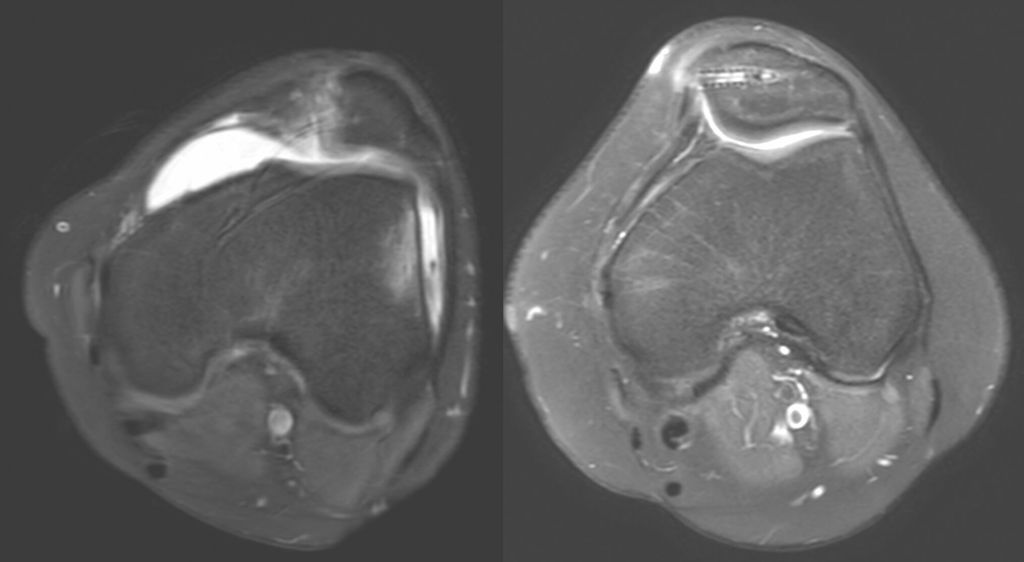

Eine Instabilität bis circa 30° ohne weitere Auffälligkeiten in der radiologischen Untersuchung wird mittels alleiniger MPFL-Rekonstruktion stabil. Ab circa 0–60° Instabilität gibt es zumeist Probleme mit der knöchernen Führung. Dies kann aufgrund eines zu späten Eingleitens der Patella – einer Patella alta – und/oder des Fehlens einer knöchernen Führung (Trochleadysplasie) auftreten. Unserer Meinung nach bedarf es einer Korrektur der Patella alta ab einem Caton-Deschamp-Index >1,2 (Abb.1) und/oder einer LTI (laterale Trochleainklination) von <17° (Abb. 2). Ab 60° ist zusätzlich ein Problem im Bereich des Alignments wahrscheinlich. Bei einer vermehrten Innenrotation des Femurs und der Tibia bei ca. 35° und/oder valgischer Beinachse ab ca. 5° wird eine Korrektur in Erwägung gezogen (Abb.3). Prinzipiell sind wir bei einer Alignmentkorrektur eher zurückhaltend (von manchen Autoren wird bereits eine Korrektur ab 20° Innenrotation empfohlen).5 Ein vermehrter TTPCL-Abstand (lateraler Kraftvektor der Patella) ab circa 24mm kann die Luxation ebenfalls begünstigen und bei einer Patella alta mitkorrigiert werden. Sollte eine knöcherne Stabilisierung notwendig sein, ist bei der Trochleaplastik eine arthroskopische oder offene Technik möglich.

Ablauf der arthroskopischen Trochleaplastik